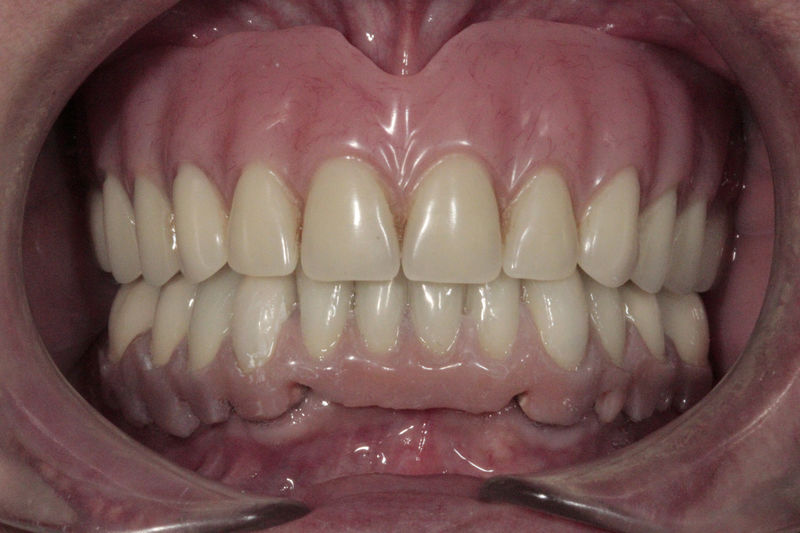

Amplia gama de tratamientos para mejorar la apariencia de la sonrisa, corrigiendo el color, la forma, el tamaño, la alineación y la posición de los dientes. Los procedimientos más comunes y solicitados incluyen el blanqueamiento dental, las carillas y coronas, así como las resinas.

Restauraciones fabricadas en el laboratorio con materiales estéticos, los cuales cubren de manera total dientes anteriores y posteriores. Se utilizan primariamente para restaurar dientes con caries, fracturas y/o defectos amplios, así como soportes de puentes. Para poder enviar el caso al laboratorio se toman impresiones utilizando materiales de impresión o técnicas modernas digitales.

Cirugía ortognática, implantes, carillas y coronas,